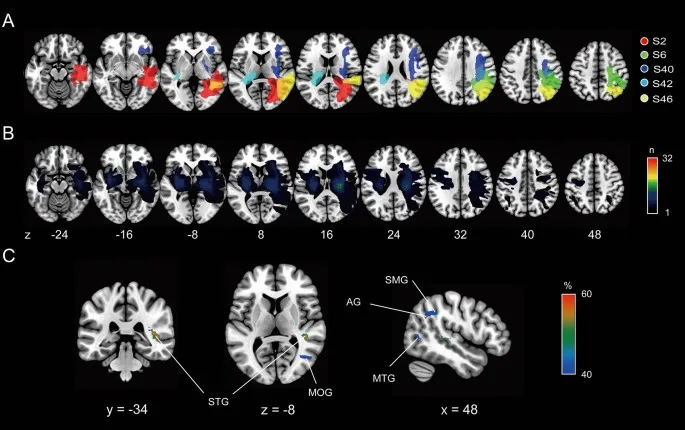

Анализ локализации поражений мозга

Чтобы identify location поражения, responsible за abnormally reduced TDE у patients с инсультом, мы сначала провели analysis subtraction поражения. Мы classified patients с инсультом либо в normal TDE группу, либо в abnormal TDE группу, используя point cutoff, определенный по TDE здоровых controls.

Ключевые области мозга

Карта subtraction (отображаются только вокселы с вероятностью > 40%) показала, что patients с abnormally reduced TDE tended иметь частые damage с центром в правой occipitotemporal коре, specifically в superior (STG) и middle (MTG) temporal извилинах, middle occipital извилине (MOG) и inferior parietal дольках, включая supramarginal извилину (SMG) и angular извилину (AG). Пиковый воксел (вероятность = 67%) был расположен в правой MTG [Координаты Montreal Neurological Institute (MNI): x = 42, y = −34, z = 8]. Эти результаты suggest, что поражения в правой occipitotemporal коре могут introduce reduction в зависящем от наклона перцептивном искажении ориентации оси тела у patients с инсультом.

Наши findings contribute к лучшему пониманию нейроанатомии тело-центрированного пространственного кодирования во время наклона всего тела.